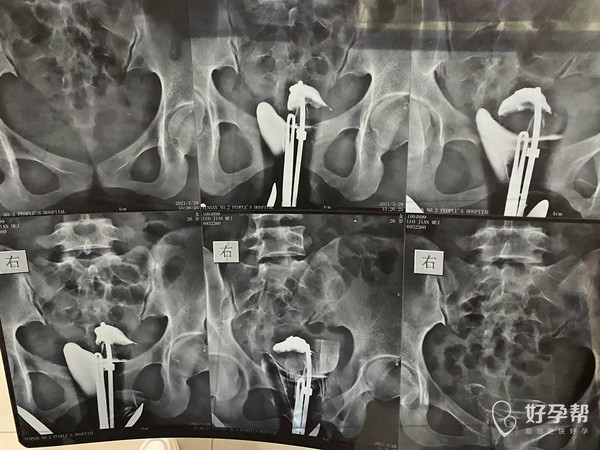

最近做输卵管造影显示输卵管堵塞疏通的概率很低

最近做输卵管造影显示输卵管堵塞,疏通的概率很低,当地医生建议直接,本人是hiv患者(病载为0)想请问哪里有可以为hiv患者做试管的医院?(女方)

这种必须做手术么还是取了胚胎不是非要做

这个手术不是非得要马上做,需要根据你的年龄、生育计划等来综合评估并权衡利弊后再决定是否需要手术以及什么时候做。如果是做试管通常为了避免输卵管积液及炎症因子逆流至宫腔影响胚胎着床等,会行输卵管结扎等手术,这个手术通常在移植前完成